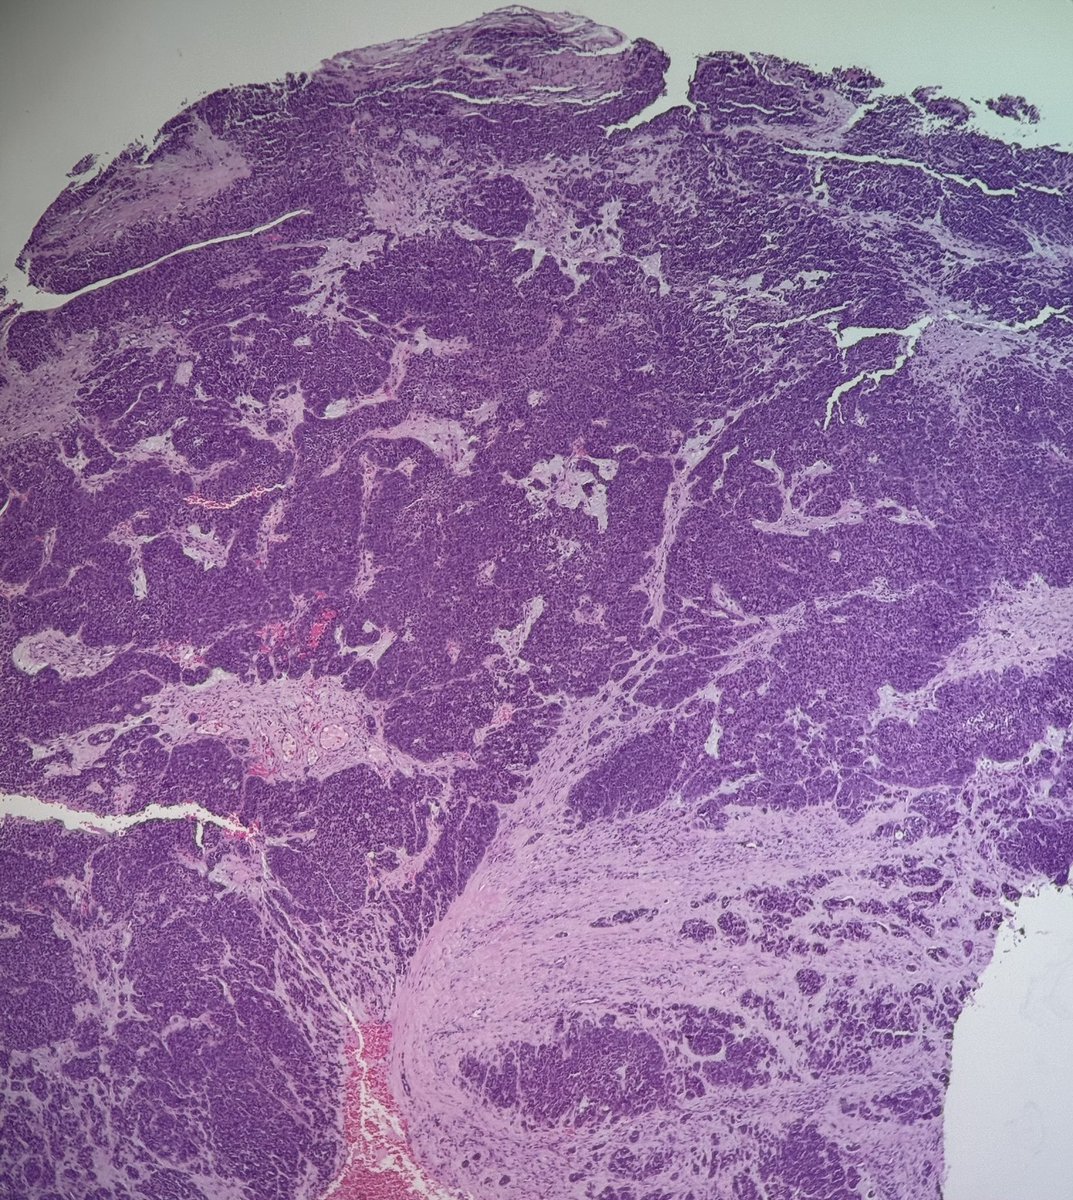

59-year-old woman with a destructive sinonasal tumor. Liver and iliac mets on CT. Biopsy performed (more pics below). Diagnostic opinions are welcome! #pathology #PathTwitter #surgicalpath #oralpath #entpath